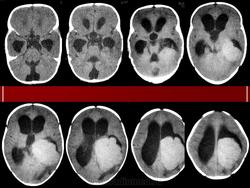

Папилломы сосудистых сплетений.